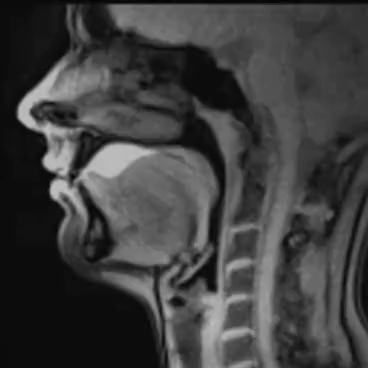

Active swallowing is dependent upon the precise timing of three primary phases; coordinated by the effective performance of many nerves and muscles:

•Oral Phase. Food is chewed and mixed with saliva to form a soft consistency called a bolus. The tongue then moves the bolus toward the back of the mouth.

•Pharyngeal Phase. The vocal cords close to keep food and liquids from entering the airway. The larynx rises inside the neck and the epiglottis moves to cover it, providing even more airway protection.

•Esophageal Stage. During the final stage, the bolus moves into the esophagus, the muscular tube that contracts to push the bolus into the stomach.

It is beyond the scope of the current post, but controlling the swallowing process is the autonomic nervous system (ANS). The ANS is a control system that acts mostly unconsciously and regulates bodily functions such as heart rate, digestion, breathing, pupillary response, urination, and sexual arousal. The image below demonstrates the complexity of the simple act of swallowing.